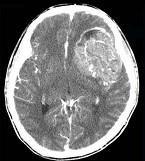

男,15岁,进行性头痛1年余,CT检查如图所示,最可能的诊断为()A.脑膜瘤B.脑血管畸形C.转移瘤D.淋巴瘤E.胶质母细胞瘤

问题 男,15岁,进行性头痛1年余,CT检查如图所示,最可能的诊断为()

选项 A.脑膜瘤 B.脑血管畸形 C.转移瘤 D.淋巴瘤 E.胶质母细胞瘤

答案 E